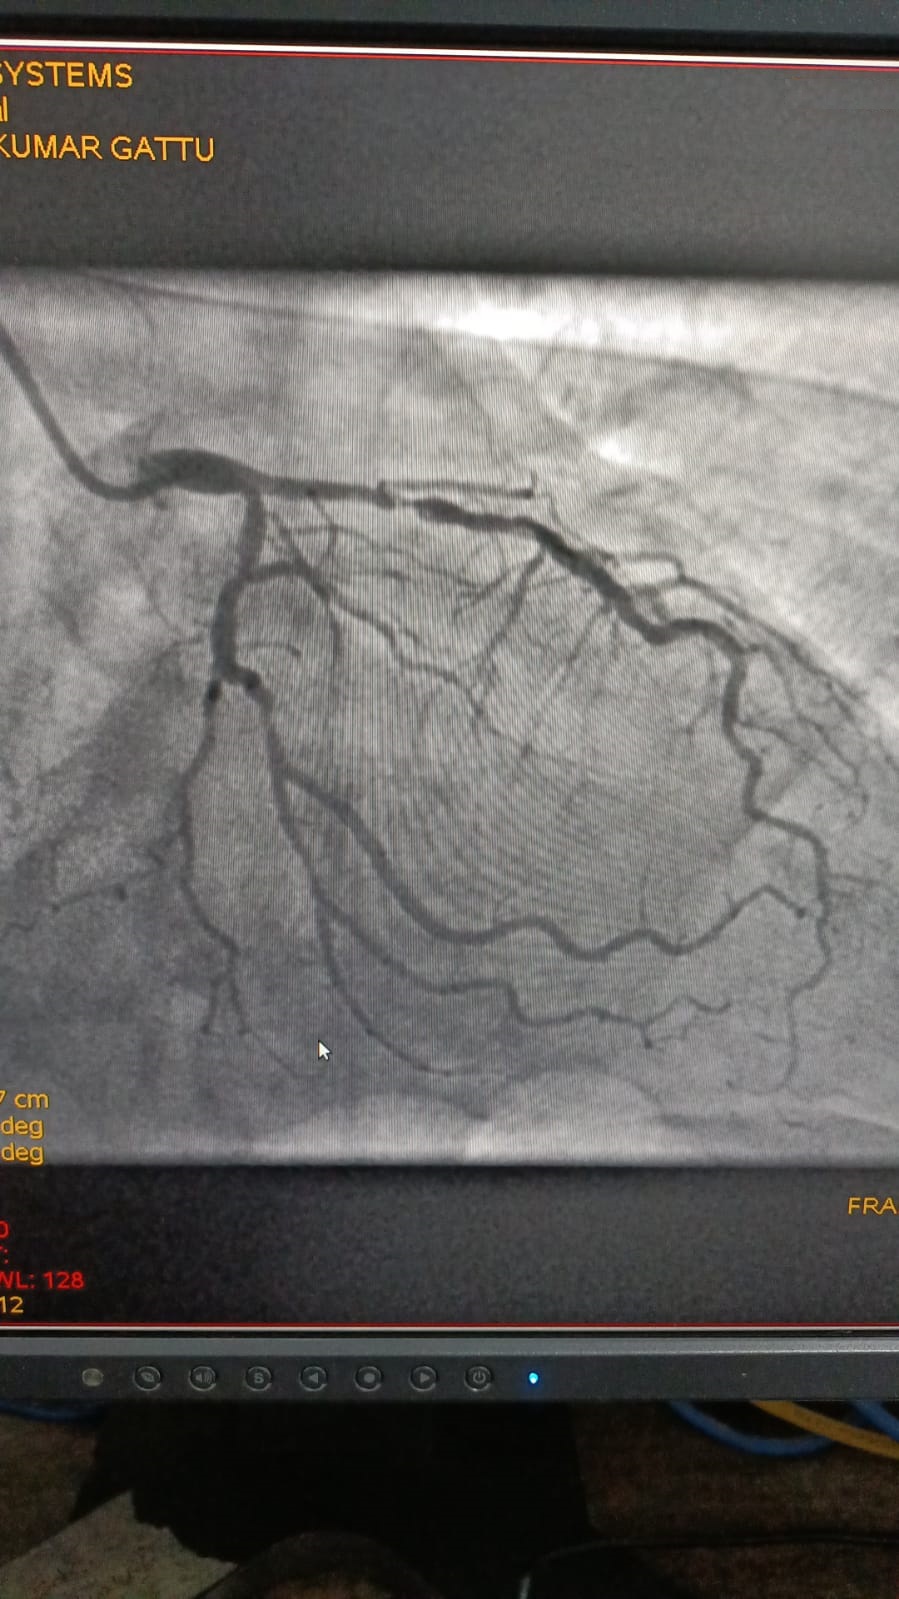

Left Coronary Artery